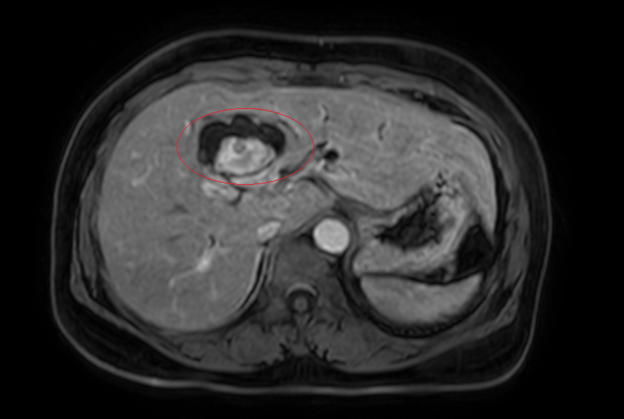

Hình 1. Hình ảnh sỏi đường mật tạo ổ áp xe gan – đường mật gan trái( vòng tròn màu đỏ). Giãn nhẹ đường mật trong gan hai bên. Dày thành nhẹ ngã ba đường mật trên phim chụp cắt lớp vi tính.

Đánh giá tổn thương trên phim chụp cộng hưởng từ: Nhu mô hạ phân thuỳ IV có ổ tổn thương dạng dịch, kích thước 38x52mm, trong có vài sỏi, sỏi lớn nhất kích thước ~27x37mm, có thông với nhánh đường mật gan phải lân cận, ngấm thuốc viền sau tiêm, chèn ép ngã ba đường mật, gây giãn đường mật trong gan hai bên

Hình 2. Hình ảnh giãn khu trú đường mật gan trái, tạo cấu trúc dạng nang và sỏi đường mật bên trong( vòng tròn đỏ), chèn ép kèm giãn đường mật trong gan hai bên trên phim chụp MRI